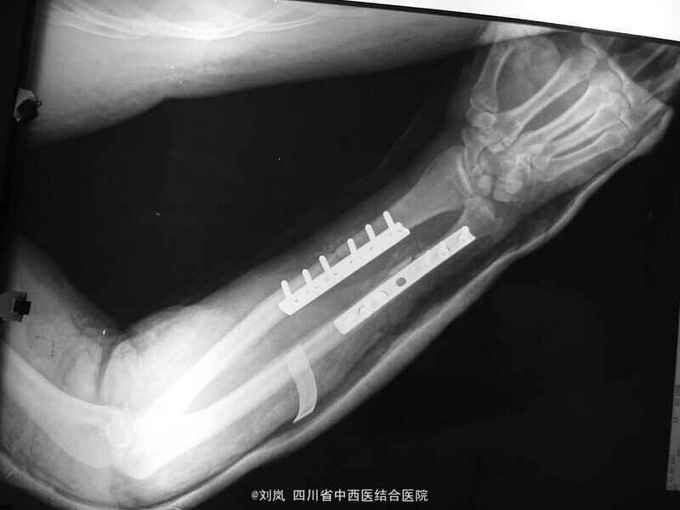

入院诊断: 1、高处坠落伤 2、脑挫裂伤 3、小肠部分坏死 小肠穿孔 肠系膜挫伤 4、右肱骨中段骨折 5、右尺桡骨中下段骨折 6、腹腔积气 7、右第7、8肋可疑骨折 8、轻度贫血 9、全身多发皮肤软组织挫伤 转入诊断: 1、高处坠落伤 2、右肱骨中段骨折 3、右侧尺桡骨中下段粉碎性骨折 4、脑挫裂伤(右,顶叶) 5、右侧桡神经损伤 6、右侧正中神经损伤 7、右侧尺神经损伤 8、右前臂Volkmann缺血性肌痉挛 9、右侧第7肋、左侧第8肋骨骨折 10、小肠部分切除、小肠修补、阑尾切除术后 11、右膝清创缝合术后 12、腹腔积气 13、轻度贫血 14、全身多发皮肤软组织挫裂伤 治疗: 患者急诊入院后,予完善检查,诊断明确,完善急诊手术准备,急诊在全麻下行了“剖腹探查:小肠坏死部分切除、小肠修补+阑尾切除术+腹腔引流术”,术后在ICU继续抗炎、止血、补液脱水监护对症治疗,并请骨科会诊后予右上肢石膏固定。 术后两周外科病情平稳,再次请骨科会诊后转骨科治疗。转入后进一步完善相关检查及术前准备,诊断明确后,在“全麻”下行了"右肱骨中段骨折切开复位内固定、右尺桡骨中下段骨折切开复位内固定术+植骨术、右侧桡神经损伤探查术",术中见桡神经挫伤明显,局部瘀血及增生组织包裹,予松解处理。术后予消肿、止痛、营养神经、预防感染等对症支持治疗,结合针灸、理疗、中药口服及康复治疗。术后伤口愈合及拆线后,予中药熏洗治疗,配合患肢主被动功能康复锻炼,住院2个月,患肢功能活动明显改善,病情好转出院。

随访:出院后定期复诊治疗,继续予药物营养神经、门诊针灸及中药治疗,术后6个月患肢感觉基本恢复正常,功能活动明显改善。 讨论:该患者损伤部位多,创伤重,并发症多,故治疗方案复杂,根据病情需要随时调整治疗重点及治疗方案。神经损伤病情判断及手术探查指征、时间如何把握?